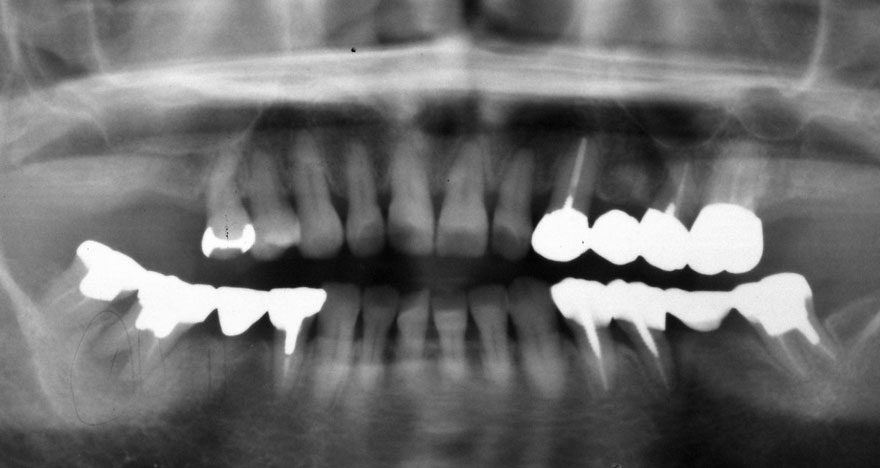

初診時 52歳 女性 平均歯槽骨喪失量:4.75mm

河田歯科医院

24年後 74歳

平均歯槽骨喪失量:6.13mm

21年間喪失量:-1.38mm

年間喪失速度:-0.057mm

(ケア頻度:1.25ヵ月ごと)